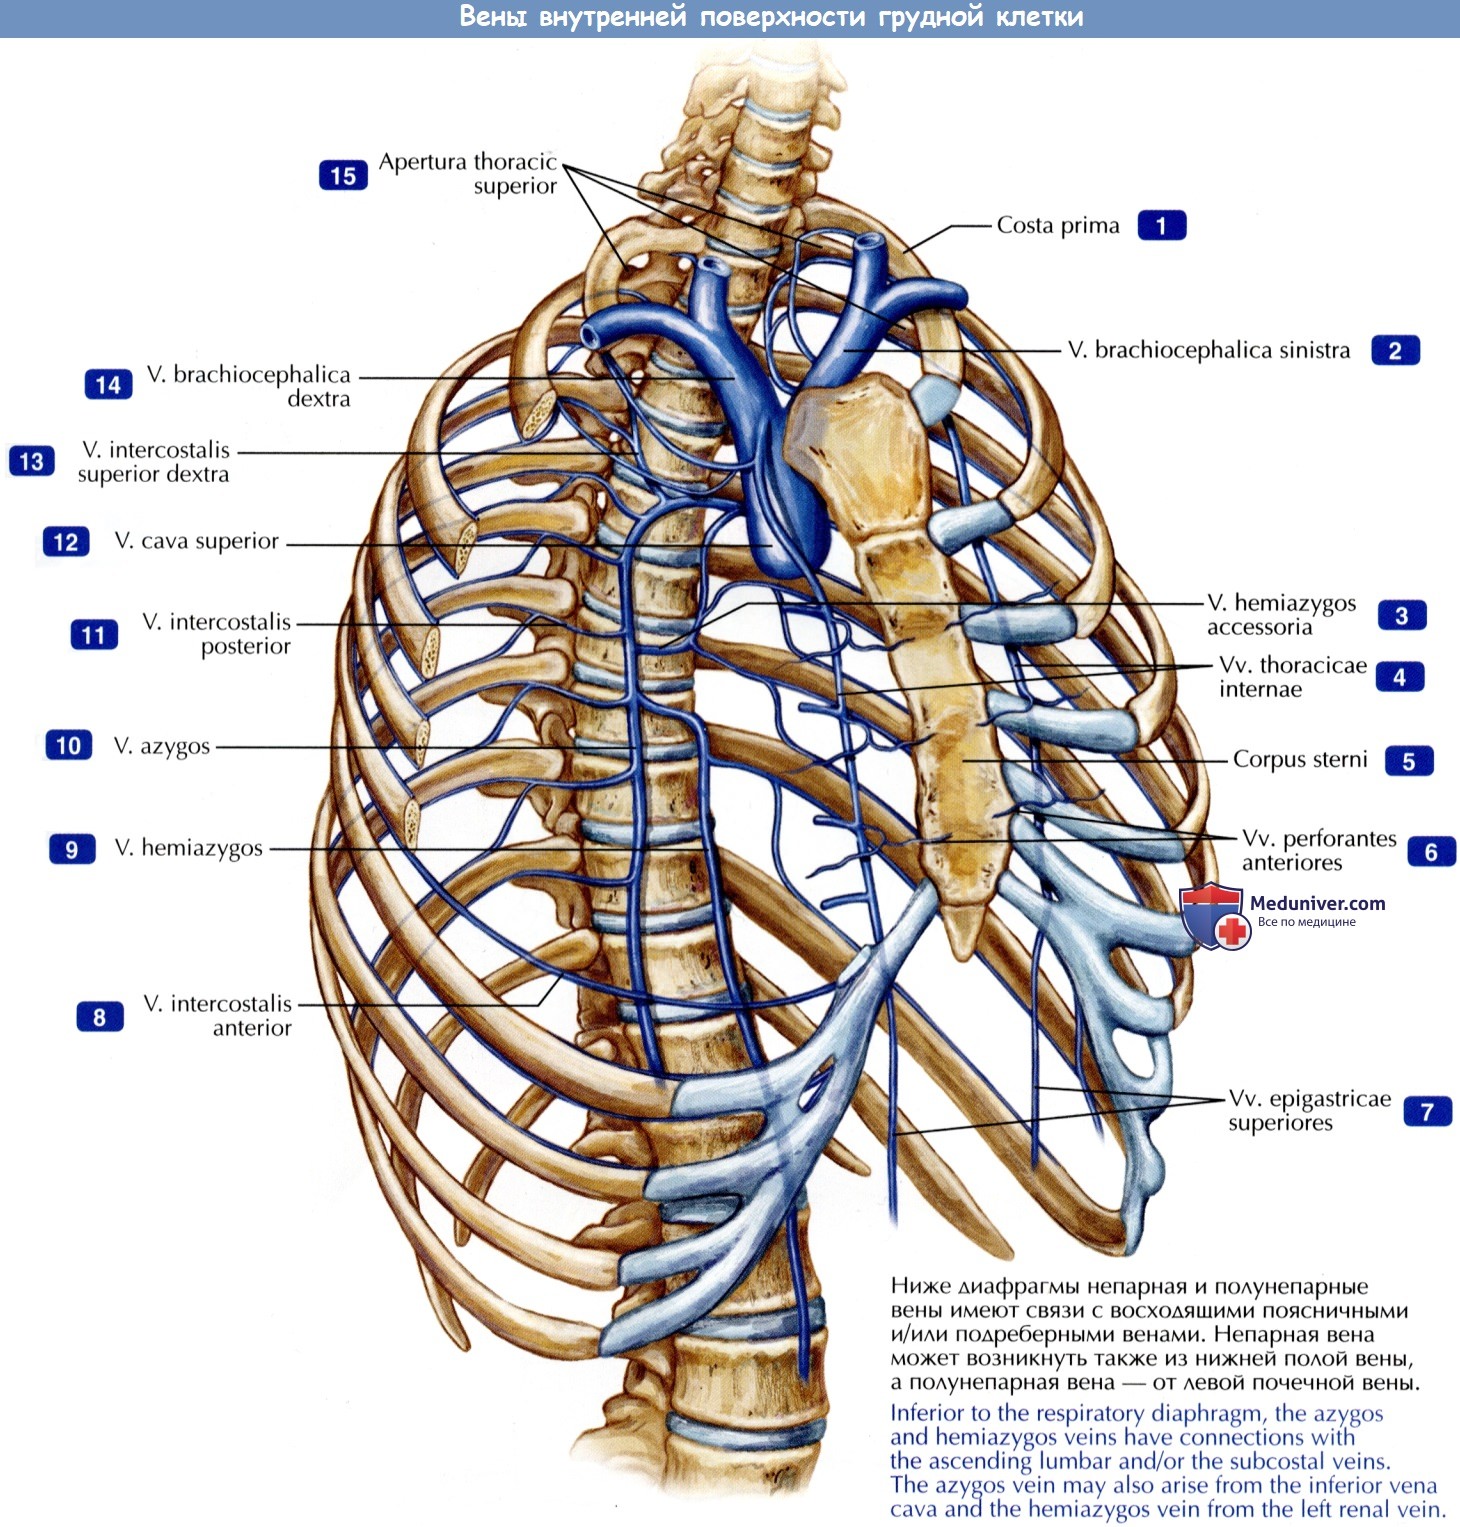

Анатомия внутренней яремной вены: КТ изображения